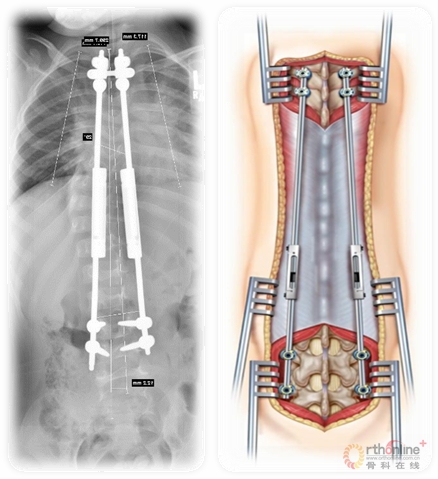

磁控生长棒技术

● Surgery:

■ Various growth-friendly surgeries are designed to follow the principles of EOS treatment outlined above, allowing the spine and chest to grow while controlling spine and chest deformity. Surgery is generally recommended if brace or cast treatment should fail to control progression, or if curve pattern does not appear amenable to brace or cast treatment.

■ Extensive thoracic spinal fusion in the very young child is associated with pulmonary compromise, and is rarely the best option.

● 手术:

■ 各种个体化的手术是为了遵循上述EOS治疗原则,使脊柱和胸部得到生长的同时控制脊柱和胸部的畸形。当支具或石膏固定控制侧凸进展失败或侧凸类型并不适合支具或石膏固定时,一般建议手术治疗。

■ 广泛胸椎融合的年轻儿童考虑到其肺部的生长,手术治疗则很少是最好的选择。